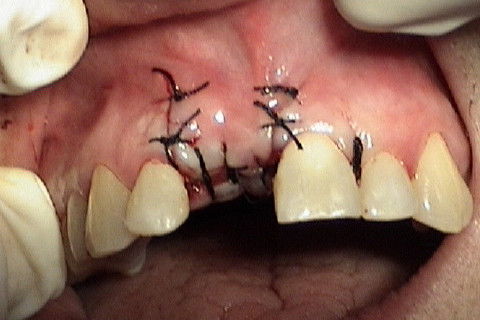

Sutura interrompida